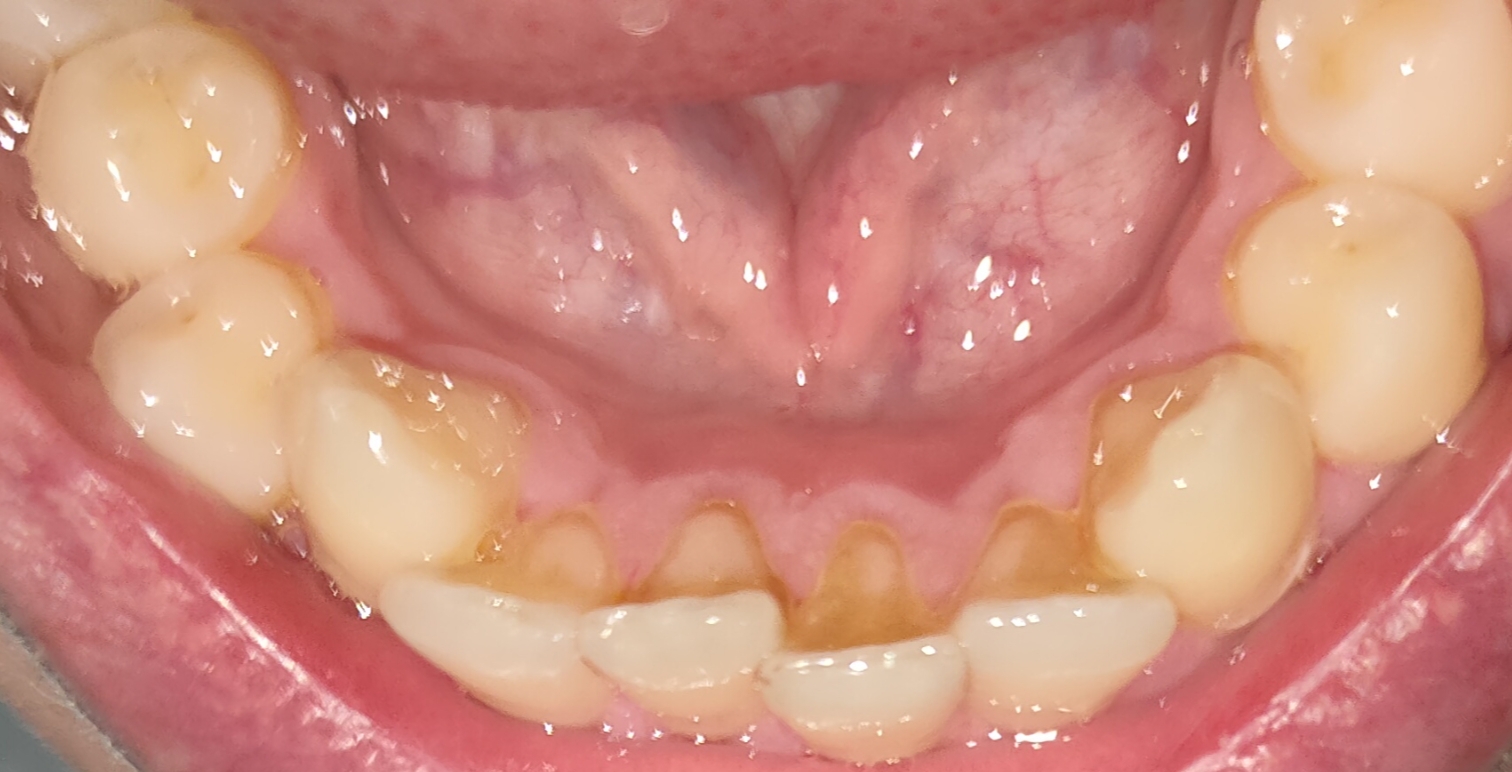

Ну че, у самого уже парадонтит, т.е нихуя не поможет, снизу зубы уже пиздец десна опустилась, сверху пару выпало просто что держаться не могут

Аноним 26/02/25 Срд 04:48:31 1604841 29